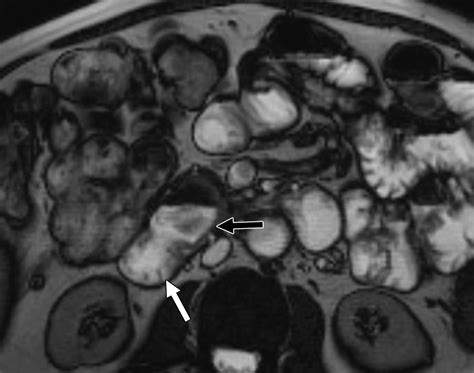

• MRI Enterography: Similar to CT enterography but uses magnetic resonance imaging instead of X-rays, making it a radiation-free option.

• Mucosal Pattern: The appearance of the lining of the small intestine, which can indicate inflammation or other abnormalities.

• Structural Abnormalities: Any visible abnormalities such as strictures, fistulas, or masses that may indicate disease.